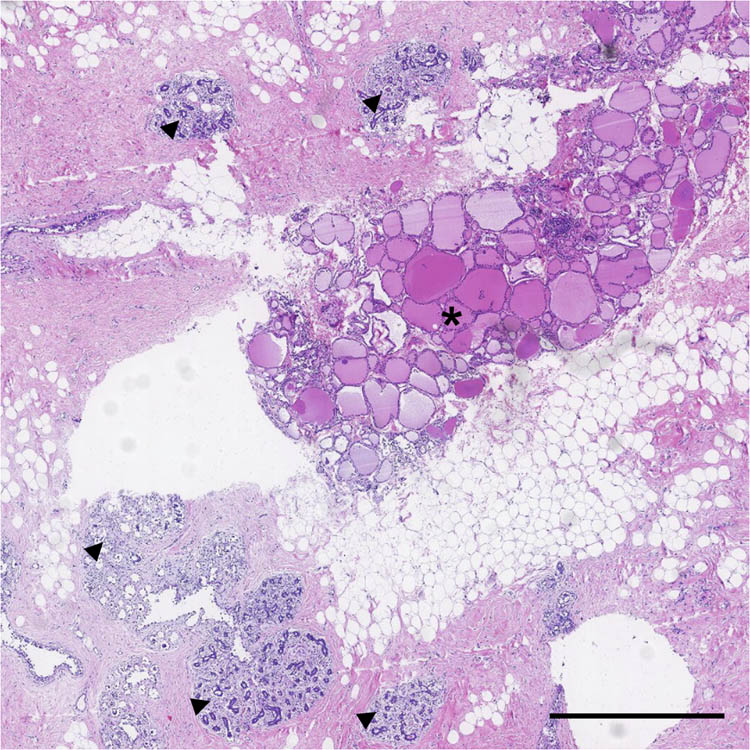

In July 2018, a 48-year-old Chinese woman came to our hospital searching for further breast cancer therapy. Before admitted to our hospital, the patient had accepted treatment in other hospital, because of left breast mass. In the previous hospital, she underwent a surgical resection of left breast mass and post-operation pathological examination confirmed left breast invasive ductal carcinoma. For further treatment, she came to our hospital. The patient had no history of other malignancy, smoking, or drinking history. She had no family history of any cancer or thyroid diseases. When she was admitted to our hospital, there were no inflammatory signs and no anemia or dyspnea. Physical examination indicated a surgical incision in the outer lower quadrant of left breast, 5.6 cm away from nipple. There were also touchable enlarged lymph nodes in the left axillary. The thyroid ultrasound scan did not find any nodules. The thyroid function tests were normal: thyrotropin (TSH) 1.51 µIU/mL (0.49–4.91 µIU/mL), free thyroxine (FT4) 10.49 pmol/L (7.64–16.03 pmol/L), and free triiodothyronine (FT3) 4.76 pmol/L (3.28–6.47 pmol/L). Because the patient had been diagnosed as breast carcinoma by pathological examination, she received modified radical mastectomy in our hospital. After surgery, the excised breast tissue went on pathological examination to confirm the pathological type of tumor. A touchable hard area in the outer upper quadrant was found. The transection of this hard area showed colors of sallow, different from the neighboring tissue. To further explore the histological characteristics, this area was sliced and performed HE staining. The HE staining image (Figure 1) showed mammary gland structures including glandular acinus and cystic hyperplasia, which accompanied usual ductal hyperplasia and columnar cell lesions. Moreover, the thyroid-like structures were found besides the breast tissue and was precisely the tissue of the color of sallow which was mentioned above. The thyroid tissue regions had obvious thyroid-like follicles that containing pink colloid and were surrounded by cells with similar character of thyroid follicular epithelial cells (Figure 2a). There were no cancer cells found in all slices. To explore whether the regions were thyroid tissues, immunohistochemistry (IHC) staining was performed. IHC staining indicated that thyroglobulin (TG) distributing in thyroid follicles, suggesting the origin of thyroid tissues (Figure 2b). Thyroid transcription factor-1 (TTF-1) expressed in cells which surrounding follicles revealed follicular cells (Figure 2c). Thyroid peroxidase (TPO) existed in the apical membrane of the thyrocyte further confirmed ectopic thyroid gland (Figure 2d). Negative staining of biomarkers such as Ki67 and Galectin-3 excluded possibility of thyroid cancer (data not shown).

Ectopic thyroid tissue found in breast. Hematoxylin and eosin (HE) staining shows thyroid-like structure (*) and breast structure (triangles). The scale bar is 1 mm.